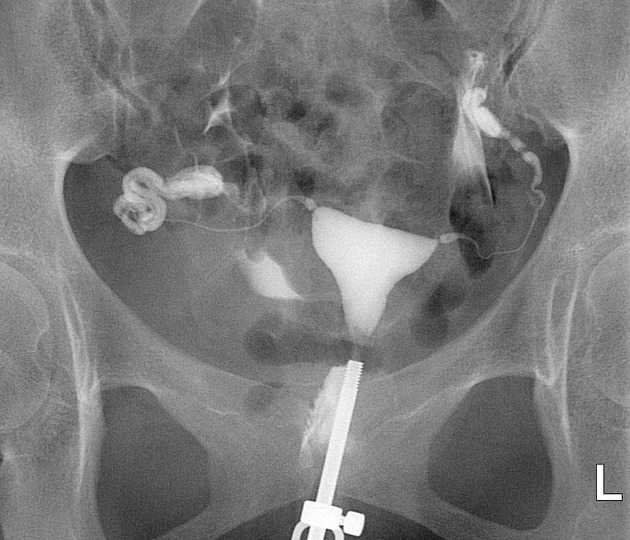

Медицинские снимки: Проходимость маточных труб

Раздел: Кадры-подсказки